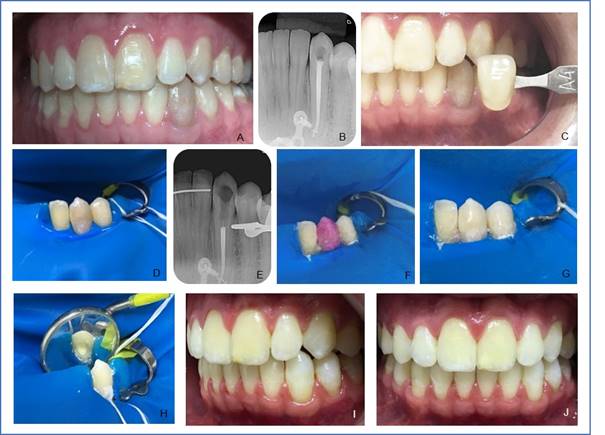

Reporte de Caso Clínico 1: individuo de sexo masculino, 23 años, con Síndrome de Treacher Collins registrado en el Hospital de Reabilitação de Anomalias Craniofaciais da Universidade de São Paulo (HRAC/USP), reportó cambio cromático en el canino inferior izquierdo (33) (Fig. 1, A), constatado en el examen clínico, así como también ausencia de sintomatología dolorosa. Se observó en el examen radiográfico tratamiento endodóntico satisfactorio (Fig. 1, B). Se procedió a la ejecución del blanqueamiento dental interno mediante la técnica mixta, fue seleccionado el color usando la escala VITA (Wilcos do Brasil, Petrópolis RJ, Brasil), (color A4), y foto intrabucal (Fig. 1, C), aislamiento absoluto (Fig. 1, D), seguido de acceso a la cámara pulpar usando la fresa diamantada nº 1012 (KG Sorensen Ind. Com. Ltda, Barueri, Brasil), desobturación endodóntica de aproximadamente 3 mm de profundidad del material obturador con condensadores nº 2 calentados en la entrada del conducto radicular, limpieza de la cavidad y confección del tampón cervical (Figura, E) con cemento ionómero de vidrio (FGM, Joinville, SC, Brasil). Luego se realizó el ataque ácido de la cámara pulpar con ácido fosfórico 37% (Biodinâmica, Ibiporã, PR, Brasil) durante 30 segundos, removido lavando con agua abundante por 60 segundos y secado con chorro de aire. Dicho paso es realizado para eliminar el "smear layer”, abrir los túbulos dentinarios y, así aumentar la permeabilidad de la dentina al agente blanqueador. El gel peróxido de hidrógeno 35% (Whiteness HP, FGM, Joinville, SC, Brasil) se manipuló siguiendo las orientaciones del fabricante y colocado en el interior de la cámara pulpar y en la cara vestibular con el auxilio de un microbrush tamaño medio (KG Sorensen Ind. Com. Ltda, Barueri, Brasil) por 45 minutos (Figs 1, F y G); el gel se removió con agua durante 1 minuto y luego se manipuló una pasta compuesta de perborato de sodio granular (Pharmácia Specífica, Bauru, SP, Brasil) con suero fisiológico estéril en un vaso Dappen estéril, y con el auxilio de una espátula de inserción la pasta se colocó en el interior de la cámara pulpar y acomodada uniformemente (Fig. 1, H), el diente se selló con cemento ionómero de vidrio (FGM, Joinville, SC, Brasil). Al pasarsiete días, se observó resultado satisfactorio (Figs. 1, I y J) al compararse con el aspecto del inicio del blanqueamiento dental. El diente recibió el medicación con pasta de hidróxido de calcio Calen (sswhite Duflex, São Cristovão, RJ, Brasil) y la restauración provisional con cemento de ionómero de vidrio (FGM, Joinville, SC, Brasil). Paciente se quejó de la coloración amarillenta de los demás dientes y entonces, fue referido para el blanqueamiento externo en el sector de Odontología Estética del HRAC/USP y restauración definitiva.